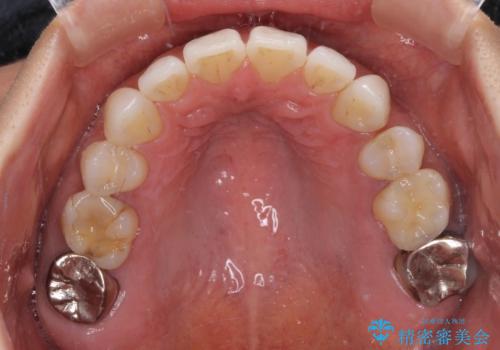

抜歯矯正の後戻りをインビザライン・ライトで解消

- 下顎前歯を中心に、以前行った矯正治療の後戻りが気になるとのことで来院された患者様です。

後戻りは軽度であったため、インビザライン・ライトにて治療を行うこととしました。

矯正治療後は、再度後戻りすることを極力回避するために、下顎前歯の舌側を細いワイヤーを用いて保定することとしました。